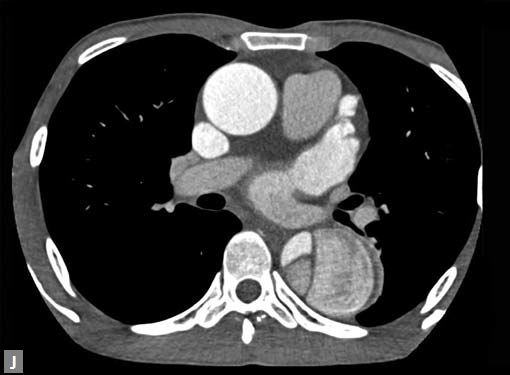

Connective tissue disease, hypertension and iatrogenic (Figs 19K to L) injury are the common causes for dissection. Radiologist not only establishes the diagnosis, also evaluates the extent of dissection, presence of thrombosis particularly in false lumen. In case of type A dissection, involvement of aortic root is determined. Relation of thrombosed lumen and ostia of coronary vessels, cephalad branches (Figs 19N, R to V) of aorta is determined. Most of the occasions membrane is demonstrated. Spiral nature of the membrane can be seen

Figs 19A to Y (A to C) Scannogram (A), plain (B) and contrast study (C) show partial anomalous pulmonary venous connection; (D to F) Heterotaxy; (G) Aortic occlusion; (H and I) Aortic stents; (J) Aortic dissection with ‘Benz’ sign due to second dissection within the true lumen; (K, L and M) Aortic dissection with thrombus in pseudolumen following catheter angiogram; (N) Aortic dissection involving common carotid arteries and subclavian artery; (O, P, Q and R) Aortic dissection with right renal artery arising from true lumen and left renal artery from false lumen; (S, T, U and V) Stanford B dissection with extension Y to iliac vessels; (W to Y) Aneurysmal dilation of ascending aorta